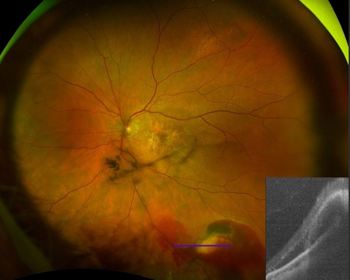

With choroidal naevi, the Optos peripheral OCT capability gives information on the height of the lesion and whether the naevus has subretinal fluid or not, which can be a sign of potential malignant transformation. Differentiating a retinoschisis from a chronic atrophic peripheral retinal detachment is another useful OCT application, guiding your decision as to whether observation or active management is required.

A peripheral exudative haemorrhagic chorioretinopathy lesion in an 80-year-old. Optos Silverstone’s image “helps confirm the lesion is not a choroidal mass but instead a subretinal/subRPE haemorrhage,” says Dr Stephen Guest